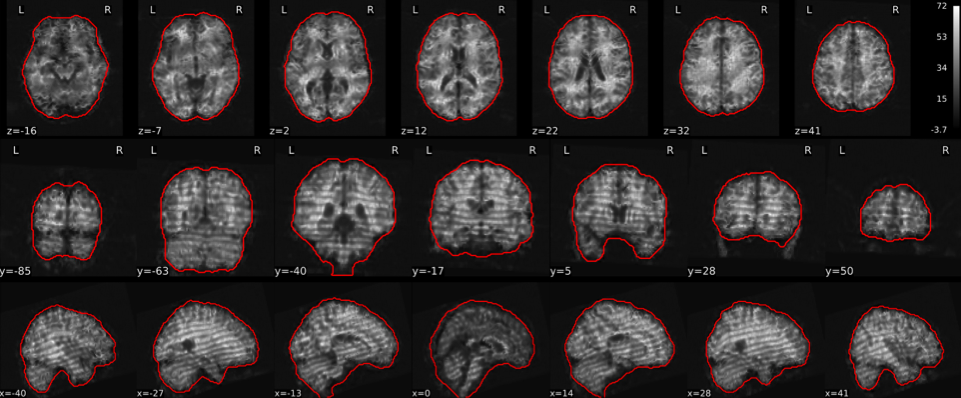

EPI tSNR

In the signal to noise ratio images of the resting state image the desired signal is compared to the amount of background noise. It is important to check all the views (sagittal, coronal, axial) because some artefacts (e.g., stripes) may be evident only in one particular view.

Example of a good subject

- Signal to noise is symmetrically distributed and there is no signal distortion

Example of a bad subject

- Asymmetry

- Potential signal distortion (might represent an artefact)

- Signal drop-out

- Stripes artefact

Clear large artefact (e.g., zebra stripes in example 1) are worth the exclusion of the subject. If you are unsure, check the other quality metrics for that subject to decide whether they should be excluded.

Summary

| good | bad |

|---|---|

| Symmetrical distribution of noise and signal | Asymmetry |

| No disruptions of the signal (no “black patches”) |

Potential signal disruptions (could be related to artefacts) |

| No stripes (sign of high motion) |

Signal drop |

| Stripe artefacts (“zebra” stripes due to motion) |